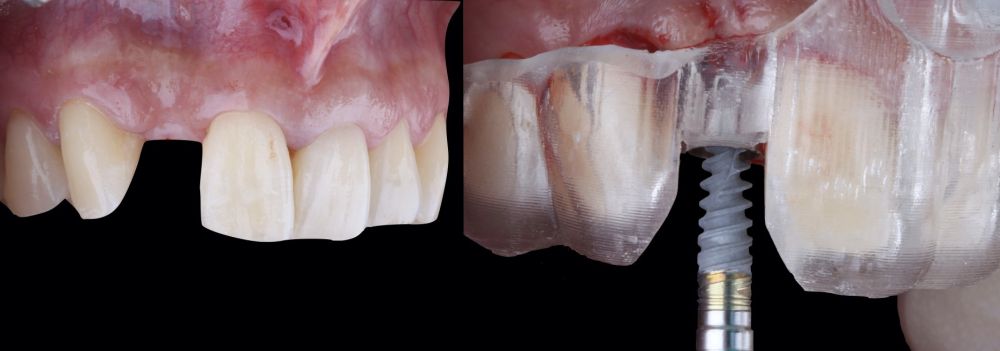

* Phase II: healing proceeded without complications. After 5 months from the alveolar preservation surgery, guided implant surgery was planned at position 1.2 (Figure 2). For this purpose, a DICOM file from cone beam computed tomography (CBCT) and an STL file obtained from scanning with an intraoral optical scanner were used. Using this information, a dental support surgical guide was fabricated (Figure 3). The surgical guide was anchored onto the teeth and guided the preparation of the implant bed and the placement of the implant. The guided surgery technique consisted of flap surgery, preparing and inserting the implant (3.5 x 11.5 mm) according to the standardised Nobel Active® guided surgery protocol (Nobel Biocare AB, Gothenburg, Sweden). Once implant 1.2 was placed,a gingival graft composed of epithelium and connective tissue from the palatal masticatory mucosa was obtained. Subsequently, the superficial epithelial layer of this graft was deepithelialised extraorally using a 15C scalpel blade in order to obtain a connective tissue graft from the underlying layer18.

The de-epithelialised graft was inserted and

positioned buccally and occlusally using horizontal mattress sutures with 5-0 non-resorbable suture (Figure 4)19.

* Phase III: three months after implant placement, the soft tissue condition was favourable (Figures 5 and 6). A digital impression was obtained using an intraoral scanner for the fabrication of a screwretained